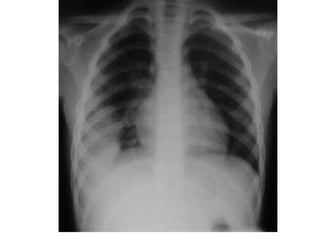

Chest x ray

Now you areready • Look at the diaphram: for tenting free air abnormal elevation • Margins should be sharp (the right hemidiaphram is usually slightly higher than the left)